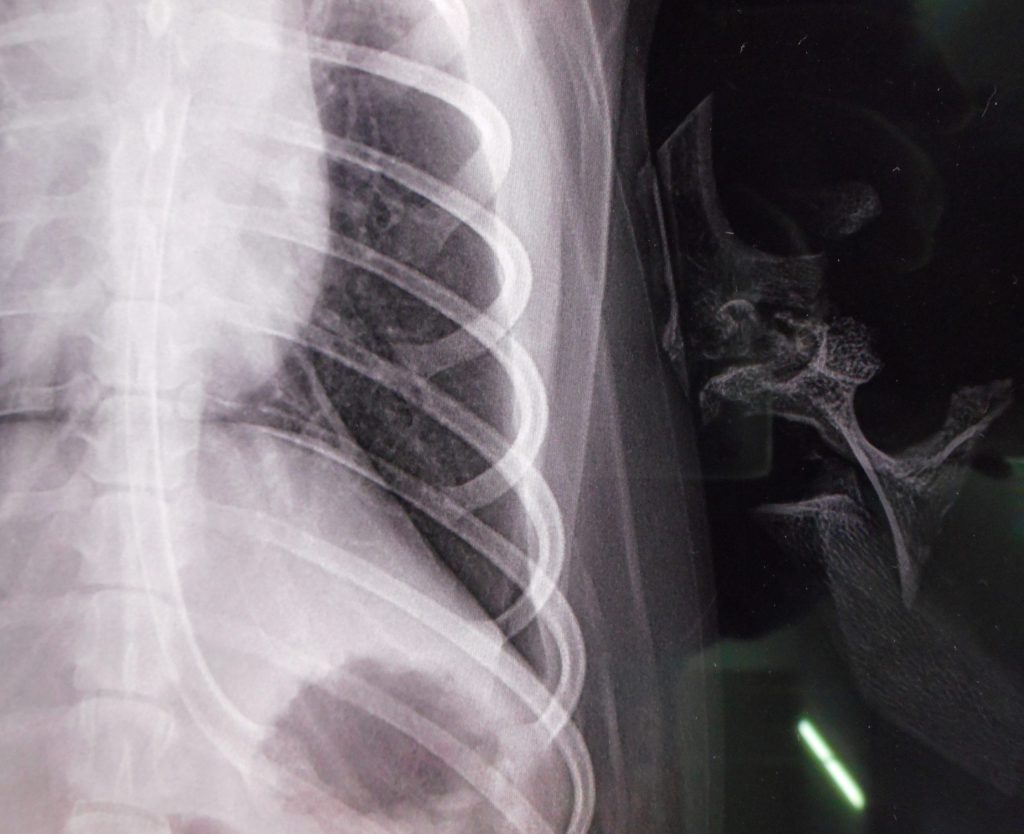

レントゲン検査です

どこにあるかわかりますか?

横にうっすら写っているのが比較のための鹿の骨

ありましたね🦴

診断:食道・胃に鹿骨閉塞

かなりの大きさで長さがある